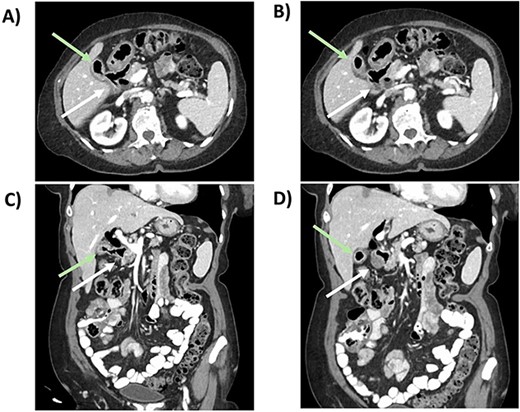

This is the case of an 86-year-old female with an independent baseline functional status and a history of hypertension and prior episodes of medically treated cholecystitis per patient preference. She presented to the Emergency Department at a public major tertiary care hospital for abdominal pain and was found to have a gallstone ileus. A CT scan showed: a gallstone in the jejunum causing a bowel obstruction proximally, pneumobilia, gallbladder wall edema, and pericholecystic fluid (Fig. 1). A nasogastric tube was placed for bowel decompression prior to proceeding for urgent operative exploration.

CT scan from the initial episode of gallstone ileus. A) Coronal CT: cholecystoduodenal fistula, B) Coronal CT: pneumobilia (superior, white dotted arrow) and air-filled gallbladder (inferior, green dotted arrow), impacted gallstone (solid white arrow), C) Axial CT: cholecystoduodenal fistula, D) Axial CT: impacted gallstone.